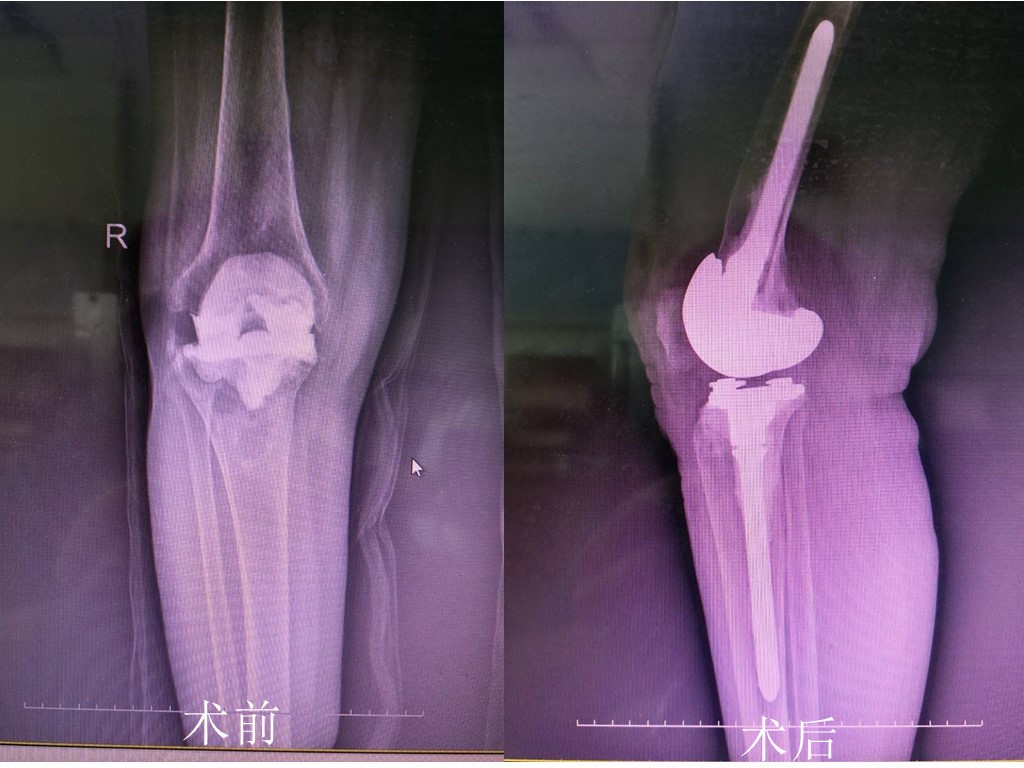

近日,我院骨五科团队成功完成了两例全膝关节翻修术,这在通辽市尚属首例,填补了我市在膝关节领域的技术空白。

两位老年女性患者,均因膝关节疼痛、肿胀3年多未愈入我院骨五科进行治疗。入院查体后,发现膝关节疼痛、肿胀,膝关节广泛压痛,膝关节活动范围小,在活动过程中膝关节全程疼痛等症状,均为行膝关节置换术后出现的不良反应。本着对患者健康高度负责的宗旨,骨五科胡中申主任组织科室人员进行病情会诊及讨论,精心制定了诊疗方案,经患者及家属同意后,决定为患者实施全膝关节翻修术。

据悉,翻修术手术技术难度较大,是初始置换术所不能比拟的。由于两位患者接受过膝关节置换术,再次行手术治疗,出血和瘢痕会出现阻碍视野;去除假体具有挑战性,每一个动作都要恰到好处,否则可能会导致严重骨缺损和假体周围骨折,不利于重建。尽管手术难度较大,但凭借着胡主任丰富的临床经验,完美重建了力线并恢复关节间隙平衡,使关节角度均达到了正常活动范围。手术效果良好,两位患者均已康复出院。